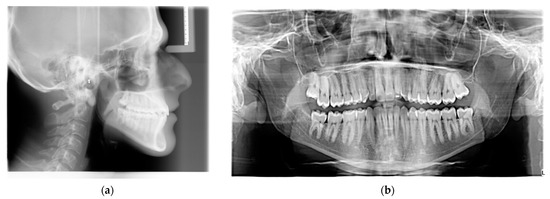

2. Case Report